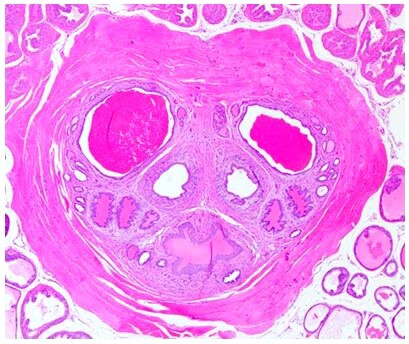

• 组织交叉TCR

组织交叉反应(Tissue Cross-Reactivity)是用于体外检测抗体药物与组织抗原表位结合的试验。其目的是确认受试抗体是否与靶组织抗原特异性结合,并检测抗体是否与非靶组织抗原发生交叉反应,从而为选择非临床安全性试验的动物种属及预测潜在毒性靶器官提供重要参考。